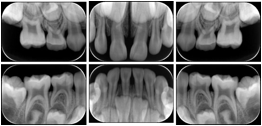

- OO-1. Intra-oral Full Mouth Series Structured Display